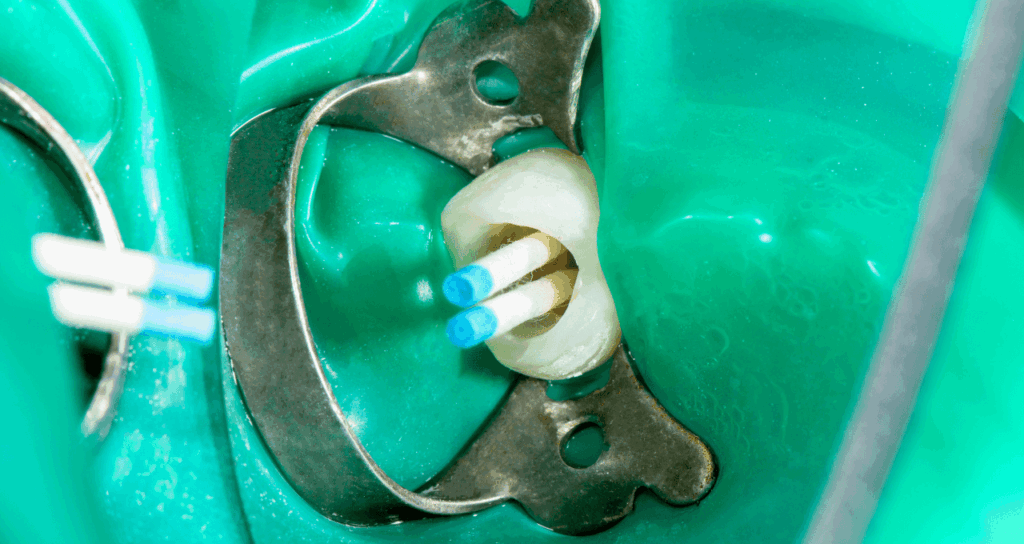

この唾液の侵入を物理的にシャットアウトするために、当院では「ラバーダム防湿」を徹底して行います。

ラバーダムとは、ゴム製の薄いシートのことです。治療する歯だけをシートの外に出し、金具で固定します。これにより、お口の中と治療部位を完全に隔離することができます。

ラバーダムの効果

- 唾液による再感染の防止

根の中への細菌の侵入を鉄壁の守りで防ぎます。 - 薬液の漏洩防止

根管洗浄には強力な消毒薬を使用します。ラバーダムがあることで、薬がお口の中に漏れて粘膜を荒らしたり誤って飲み込んだりする事故を防ぎます。 - 器具の誤嚥防止

治療に使用する細い針(ファイル)などの器具を、誤って飲み込んでしまうリスクをゼロにします。

日本の歯科医院におけるラバーダムの使用率は、残念ながら数%程度と言われています。

手間とコストがかかるため敬遠されがちですが、世界的な基準(グローバルスタンダード)では、ラバーダムなしの根管治療はあり得ません。

当院では、患者様の安全と治療の成功を最優先に考え、ラバーダム防湿を必須の処置として位置付けています。

隔壁の作製・ラバーダム防湿

虫歯で歯が崩壊している場合は、まず樹脂で壁(隔壁)を作ります。

その後、ラバーダムを装着し、患部への唾液の侵入を遮断します。